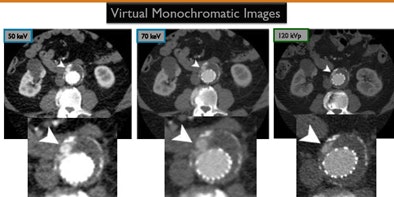

The technology "can enable processing of the dual-energy images to create virtual monochromatic images from 40 to 140 keV, and there are clear signs that using virtual monochromatic images for improving vascular enhancement is a real benefit because it gives you an additional series of monochromatic images to exploit for better diagnostic performance," Sahani said.

Virtual monochromatic images are synthesized from material density images. They depict how the imaged object would look if the x-ray produced photons at a single energy.

Examining monochromatic images acquired at 40 kV to 140 kV, for example, shows that at 50 kV there is more than twice the Hounsfield attenuation within the intravascular structures compared to standard polychromatic images, Sahani said. At 70 kV, the contrast drops, but image quality improves slightly and is still better than conventional 120-kVp images. In the case of a subtle endoleak, for example, one will be able to diagnose it more confidently in lower-keV images, and there are other techniques such as decreasing contrast volume to improve vascular enhancement.

| Above, Box and Whisker plot shows mean aortic attenuation of virtual monochromatic series (50, 70, 90, and 110 keV) generated from single-source, dual-energy CT compared with previous CTA using single-energy acquisition (120 kVp). Below, higher vascular attenuation was observed in 50- and 70-keV images compared to 120 kVp (p < 0.001). Images correspond to the four virtual monochromatic series. All images courtesy of Dr. Dushyant Sahani. |